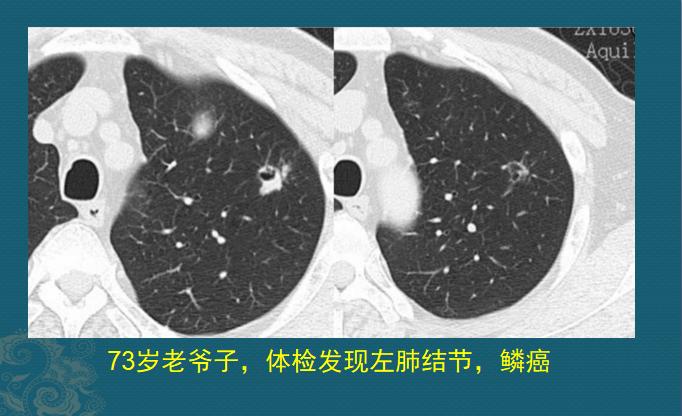

都说“73、84,阎王不叫自己去”,但有时候孝心可以续命延寿。下面这位73岁老爷子,有点小咳嗽,孩子们逼着做体检,结果发现左侧肺鳞癌,已经手术切除好几年了: